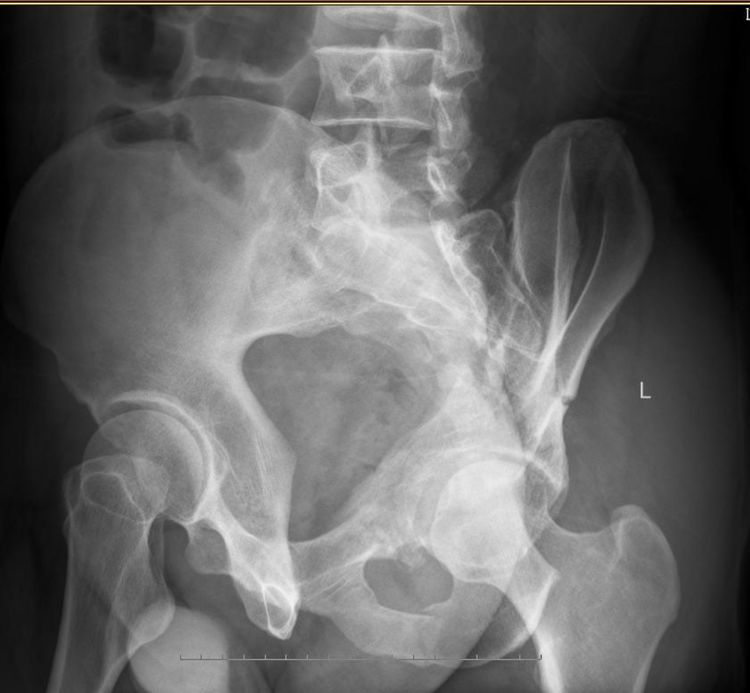

近日我骨一科就收治了一名因车祸伤至左侧髋臼双柱复杂骨折的病人。众所周知,骨盆髋臼骨折是创伤骨科最难的手术之一,髋臼骨折最复杂的类型(按Judet-Letournel 分型)就包括有前后柱的双柱骨折。

术前DR